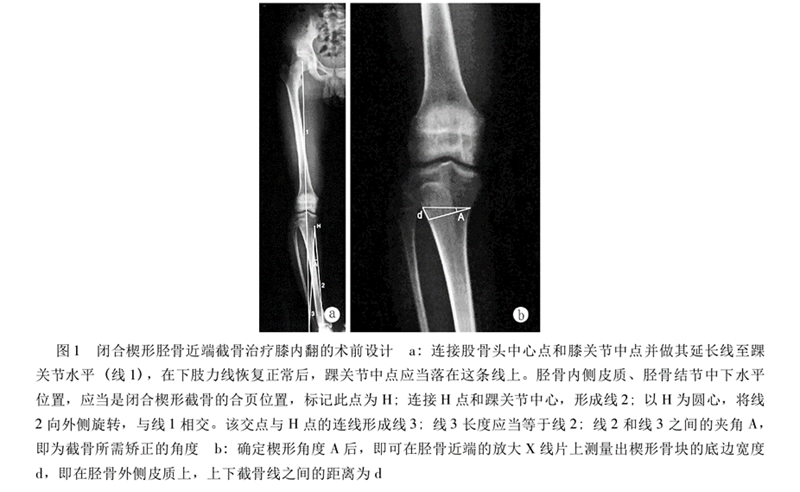

CWHTO术前计划

北京积水潭医院黄野教授等采用改良外侧闭合楔形胫骨高位截骨术治疗24例共35膝年龄均在45岁以下的膝内翻伴膝关节内侧间室轻度骨关节炎患者,术后平均胫股角(FTA)173.6°±2.4°,平均矫正11.0°±4.3°,截骨端均愈合,有1例延迟愈合。术后半年完全负重,无一例发生感染。2例出现腓总神经并发症(5.7%)。

采用改良外侧闭合楔形截骨,可以安全有效纠正内翻畸形,缓解骨关节炎疼痛,适用于年轻活跃的单侧或双侧膝内翻患者。但腓骨截骨的并发症仍然是需要考虑的因素之一。

Coventry建议内翻畸形至少矫正至股骨胫骨解剖外翻角8°;Hernigou等发现患者术后机械外翻角在3°-6°时临床效果较好;Fujisawa等发现如果HTO术后力线通过胫骨外侧平台的30%-40%,软骨破坏则不再进展,若通过胫骨平台外侧的62%,则为最佳点,此点被定义为Fujisawa点。